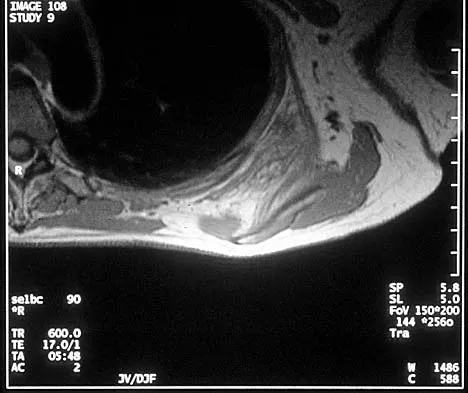

A 28-year-old man sustained numerous injuries in an accident including a dislocation of the elbow and a severe closed head injury that resulted in unconsciousness. The elbow was reduced in the emergency department. After 1 month of rehabilitation, the patient reports pain and stiffness. A radiograph is shown in Figure 23. Management should now consist of

Correct Answer: open reduction, heterotopic bone excision, anterior and posterior capsular releases, and a hinged elbow fixator.

In a young individual with a chronic dislocation of the elbow and heterotopic bone formation, the treatment of choice is open reduction, heterotopic bone excision, anterior and posterior capsular releases, and a dynamic hinged fixator to begin protected early postoperative range of motion. It is important to understand that the fixator protects the reconstruction and allows early range of motion, but it does not maintain the reduction and should not be expected to do so. Pin fixation across the elbow delays early motion and is not recommended. Total elbow arthroplasty is not indicated, and ulnohumeral arthroplasty is for a primary arthritic condition. Garland DE, Hanscom DA, Keenan MA, et al: Resection of heterotopic ossification in the adult with head trauma. J Bone Joint Surg Am 1985;67:1261-1269.